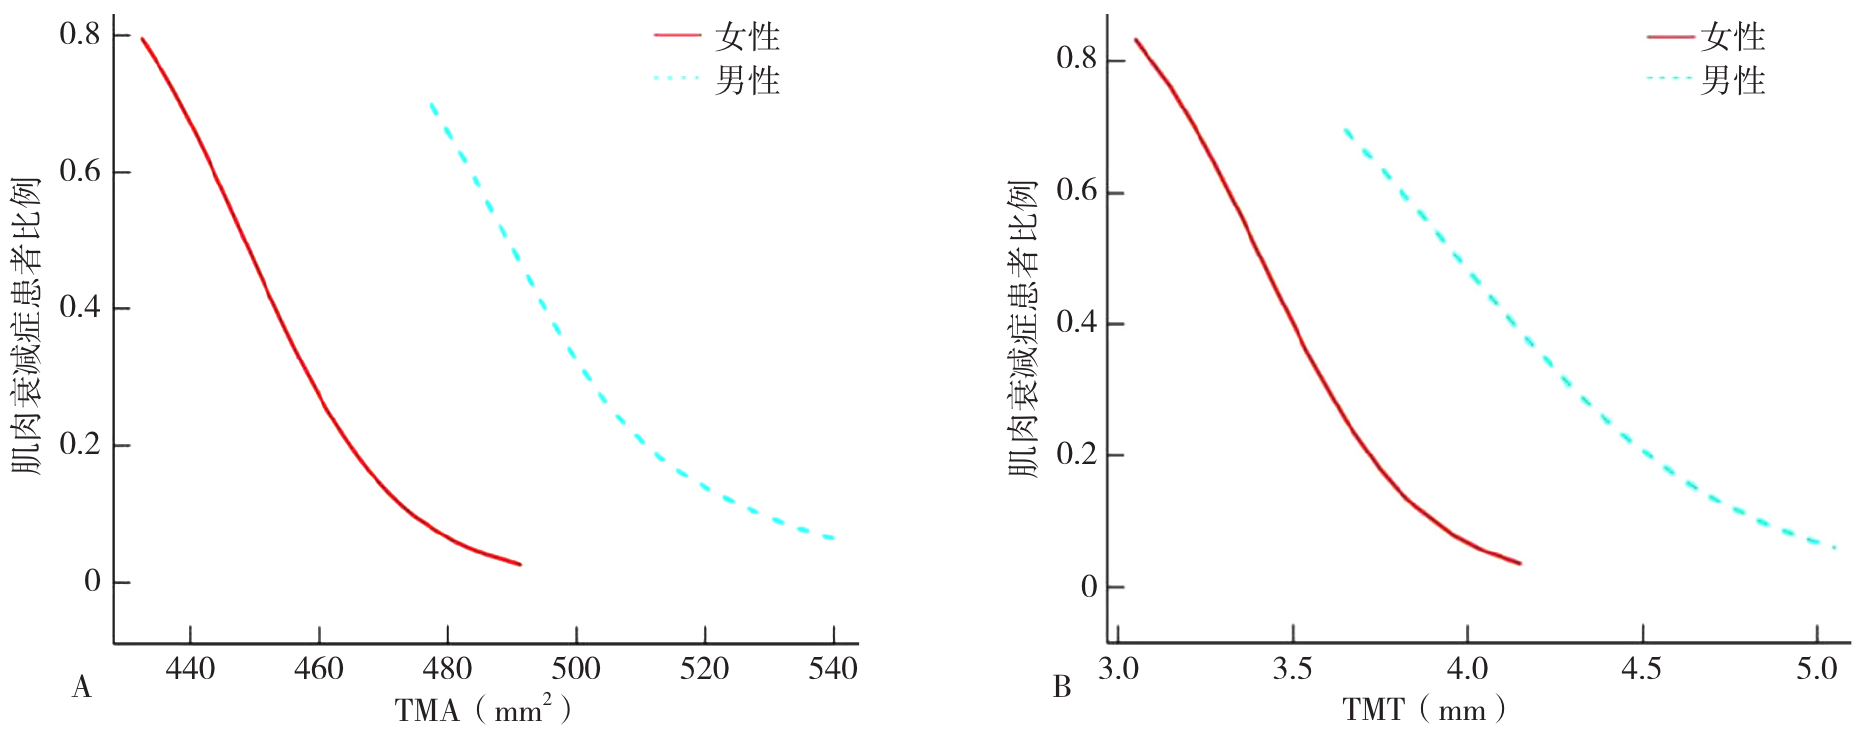

图3 不同性别急性缺血性脑卒中患者颞肌测量指标和肌肉衰减症的平滑曲线注:A为TMA指标,B为TMT指标。

Figure 3 The smooth curve of TMT and TMA and sarcopenia in patients with acute ischemic stroke of different genders